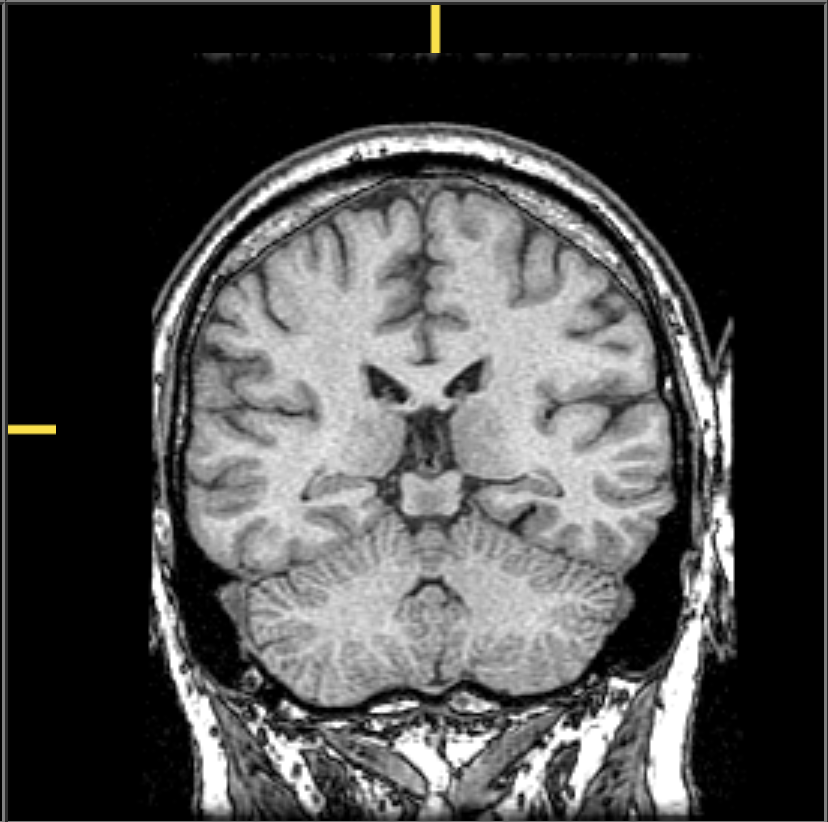

| Major division | Ventricular Landmark | Embryonic Division | Structure |

|---|---|---|---|

| Forebrain | Lateral | Telencephalon | Cerebral cortex |

| Basal ganglia | |||

| Hippocampus, Amygdala |

| Third | Diencephalon | Thalamus | |

| Hypothalamus | |||

| Midbrain | Cerebral Aqueduct | Mesencephalon | Tectum, Tegmentum |

| Hindbrain | 4th | Rhombencephalon | Cerebellum, pons |

| – | Medulla oblongata |

| Landmark | Identifies/separates |

|---|---|

| Medial longitudinal fissure (longitudinal fissure) | Divides hemispheres |

| Lateral sulcus/fissure aka Sylvian Fissure | Divides temporal lobe from frontal & parietal |

| Central sulcus aka Rolandic Fissure | Divides frontal from parietal lobe |

| Lobe | Sulci | Gyri | Areas |

| Frontal | Central sulcus | Precentral gyrus | motor cortex |

| Corpus callosum | Cingulate gyrus | anterior cingulate cortex | |

| olfactory cortex | |||

| gustatory cortex |

| Temporal | Lateral fissure | auditory cortex | |

| hipppocampus | |||

| amygdala |

| Parietal | Central sulcus | Postcentral gyrus | somatosensory ctx |

| Occipital | visual ctx | ||

| Insula | Lateral fissure | gustatory ctx |